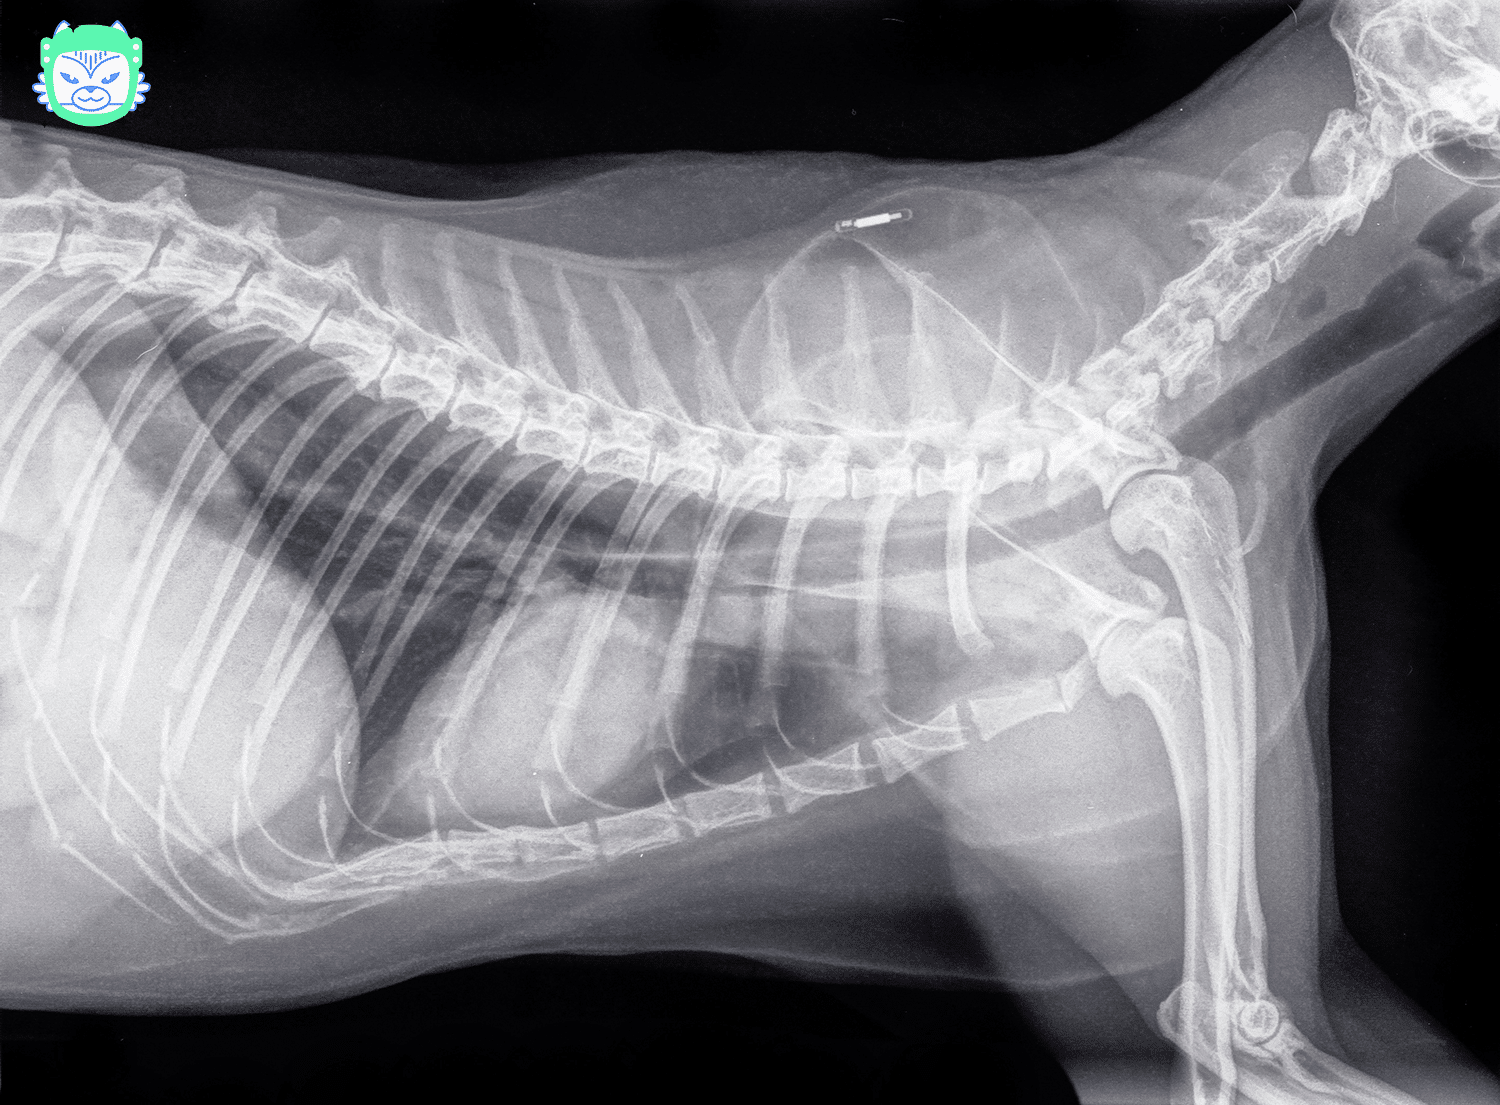

Où se trouve la puce électronique d’un chat ?

La puce électronique est généralement implantée entre les omoplates du chat, sous la peau. Elle est minuscule, à peu près de la taille d’un grain de riz, ce qui la rend difficile à sentir à la palpation.

Malgré sa petite taille, la puce contient des informations cruciales pour la sécurité de votre animal, ce qui en fait un outil d’identification puissant malgré son apparence discrète.